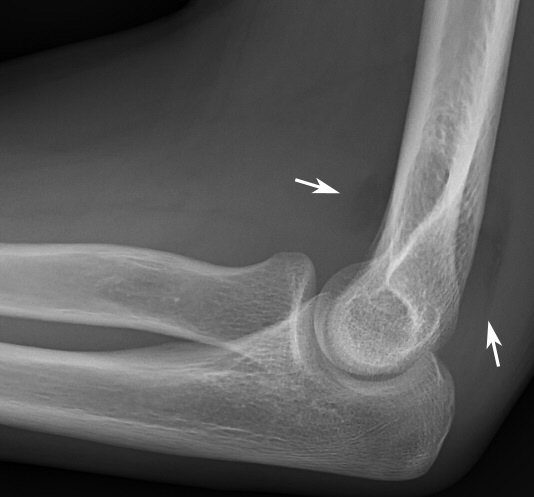

Suprakondylar humerusfraktur, Gartland 3, före och efter operation med stiftning